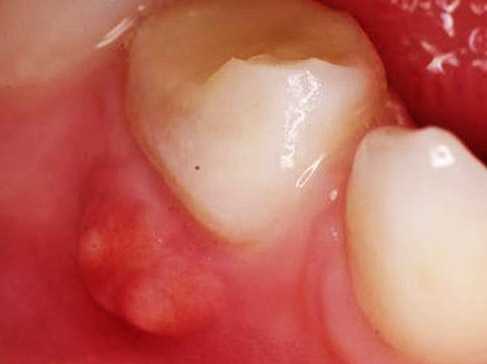

Π€ΠΎΡΠΎ: ΡΠ²ΠΈΡ Π½Π° Π΄Π΅ΡΠ½Π΅

ΠΠΈΠΏΠ΅ΡΠΏΠ»Π°Π·ΠΈΡ Π΄Π΅ΡΠ½Π΅Π²ΡΡ ΡΠΊΠ°Π½Π΅ΠΉ ΡΠΏΠΎΡΠΎΠ±Π½Π° ΠΏΡΠΈΠ²Π΅ΡΡΠΈ ΠΊ Π½Π°Π³Π½ΠΎΠ΅Π½ΠΈΡ. ΠΡΠ»ΠΈ Π½Π° Π΄Π΅ΡΠ½Π΅ ΠΏΠΎΡΠ²ΠΈΠ»Π°ΡΡ ΡΠΈΡΠΊΠ° Ρ Π³Π½ΠΎΠ΅ΠΌ, ΡΡΠΎ ΠΌΠΎΠΆΠ΅Ρ Π±ΡΡΡ ΡΠ²ΠΈΡ, ΠΊΠΎΡΠΎΡΡΠΉ ΠΏΡΠ΅Π΄ΡΡΠ°Π²Π»ΡΠ΅Ρ ΡΠΎΠ±ΠΎΠΉ ΠΏΡΡΡ Π³Π½ΠΎΠΉΠ½ΠΎΠ³ΠΎ ΡΠΎΠ΄Π΅ΡΠΆΠΈΠΌΠΎΠ³ΠΎ Π½Π°ΡΡΠΆΡ. ΠΡΠ»ΠΈ ΠΎΠ½ Π·Π°ΠΊΡΡΡ, ΠΈ Π³Π½ΠΎΠΉ Π½Π΅ Π²ΡΡΠ΅ΠΊΠ°Π΅Ρ, ΡΡΠ²ΡΡΠ²ΠΎ Π±ΠΎΠ»ΠΈ ΠΌΠΎΠΆΠ΅Ρ Π±ΡΡΡ Π½Π΅ΡΡΠ΅ΡΠΏΠΈΠΌΡΠΌ. ΠΠΎ ΠΌΠ΅ΡΠ΅ ΠΏΠΎΡΡΠ΅ΠΏΠ΅Π½Π½ΠΎΠ³ΠΎ Π²ΡΡΠ΅ΠΊΠ°Π½ΠΈΡ ΠΆΠΈΠ΄ΠΊΠΎΡΡΠΈ ΠΈΠ· ΠΎΡΠΊΡΡΡΠΎΠ³ΠΎ ΡΠ²ΠΈΡΠ° ΡΠ΅Π»ΠΎΠ²Π΅ΠΊ ΡΡΠ²ΡΡΠ²ΡΠ΅Ρ ΠΎΠ±Π»Π΅Π³ΡΠ΅Π½ΠΈΠ΅.